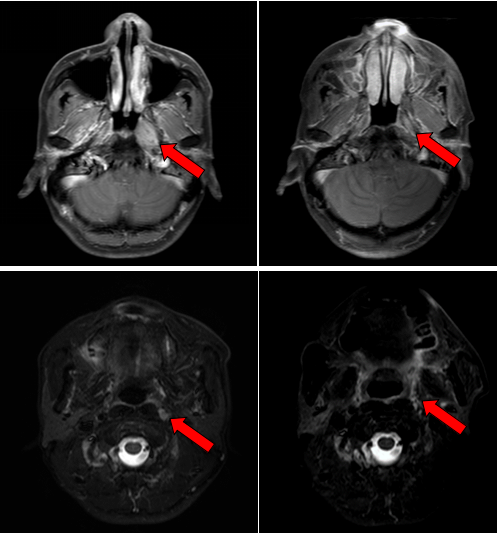

治疗前后鼻咽部病灶、咽后淋巴结病灶对比( 左:治疗前,右:治疗后)

2016年7月,患者因左侧耳鸣一个多月到医院就诊,经过一系列检查,最终确诊为鼻咽非角化性癌,分期为T3N1M0 Ⅲ期,属于局部晚期鼻咽癌。我院鼻咽癌诊治中心邱素芳主任医师团队接诊后,为其量身制定了“诱导化疗+同步放化疗+辅助化疗”综合方案,在放疗环节凭借精细靶区勾画与剂量调控,实现“精准打击”。治疗结束后复查,肿瘤已基本退缩。